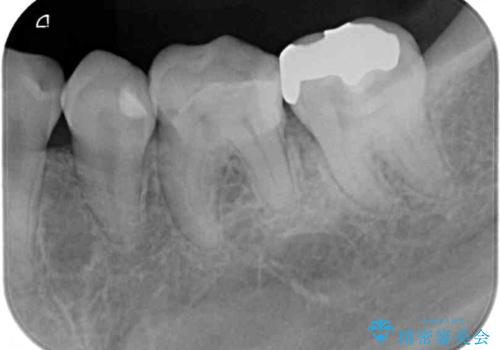

- 奥歯の詰め物や周辺の歯が欠けてしまったとのことで来院された患者様です。

上顎は、元々の詰め物が小さく、欠けた範囲も大きくなかったため、セラミックインレーにて修復治療を行うこととしました。

一方下顎は、元々のむし歯の範囲が広かったため、長期的な予後を踏まえ、セラミッククラウンにて補綴治療を行うこととしました。